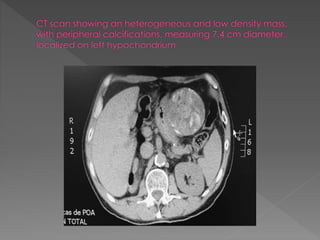

An article inthe Gurdian newspaper UK in March 2013 claimed that “five worst medical” nightmares a Pt faces, three related to surgery: 1. Wrong site surgery 2. Wrong patient surgery 3. Retained instruments and swabs The rate of harm in surgical patient is unknown but probably occur in about 10% surgical patient, though much of this harm will be minor.

1. Wrong patientin the operation theatre. 2. Surgery performed in the wrong side or site 3. Wrong procedure 4. Failure to communicate changes in the patient condition. 5. Disagreement about proceeding. 6. Retained instruments or swabs.